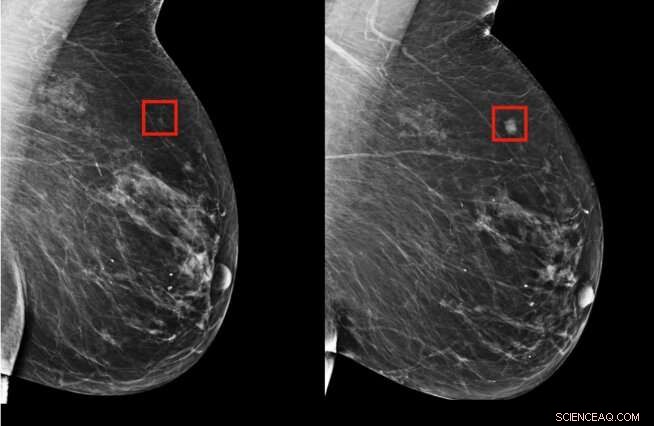

The team's model was shown to be able to identify a woman at high risk of breast cancer four years (left) before it developed (right). Credit: Massachusetts Institute of Technology

The team's model was significantly better at predicting risk than existing approaches: It accurately placed 31 percent of all cancer patients in its highest-risk category, compared to only 18 percent for traditional models.